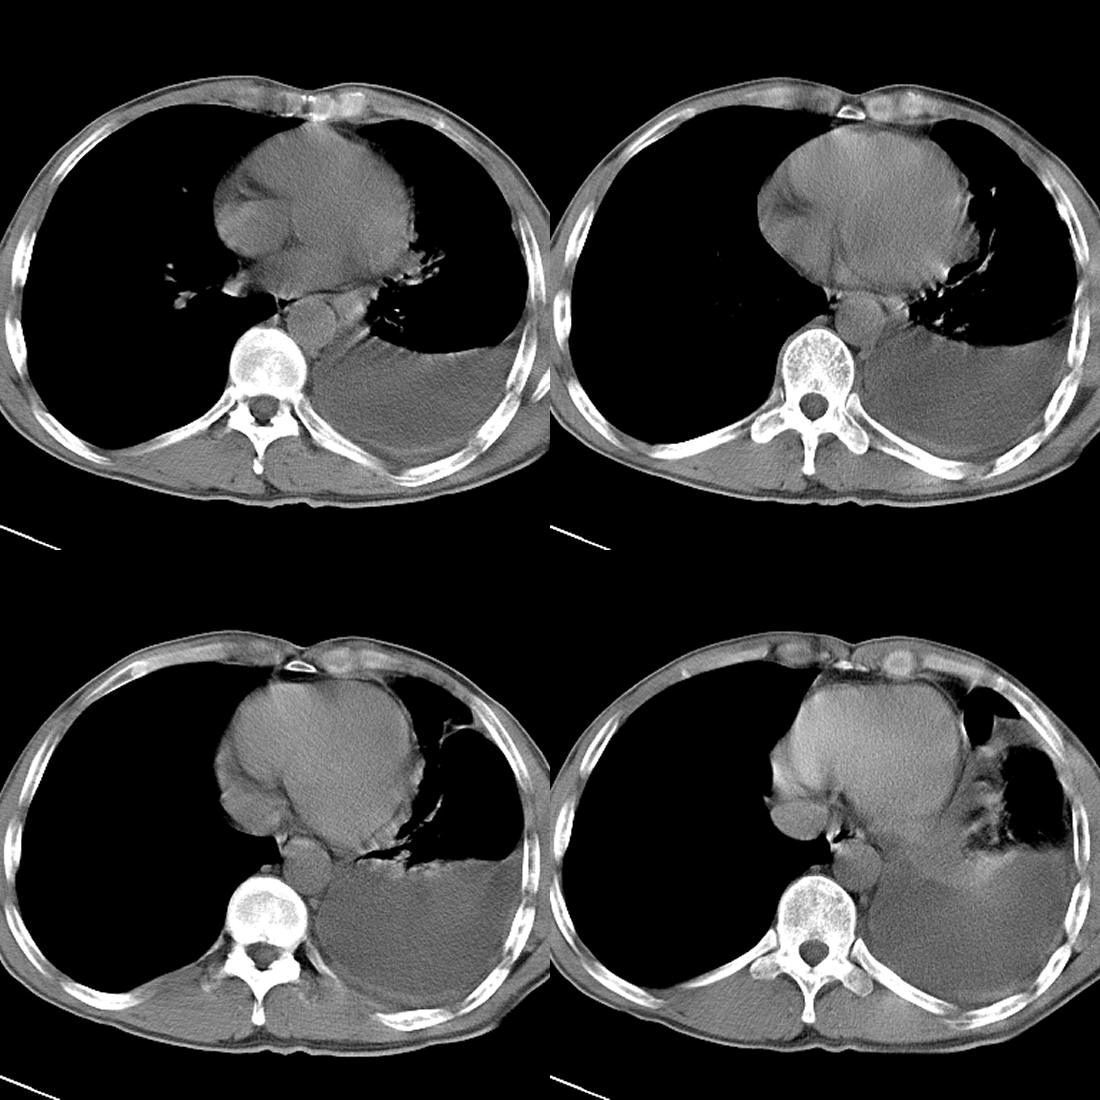

m42y,反复胸背痛数月。无明显的咳嗽、咯痰、咯血症状。

左肺上叶周围型肺癌伴肺\\胸膜\\肋骨\\胸椎横突转移,左侧胸腔积液.

左侧椎体、横突、肋骨呈溶骨性破坏,半左侧胸腔中等量积液;左肺尖部可见一肿块影,边界欠清;多考虑恶性骨肿瘤,不除外肺尖部转移性表现可能。

左肺没见明显占位病变,但左肺门增大,不除外肿大淋巴结,左侧肋骨、胸椎融骨性破坏,考虑左侧胸膜恶性病变

左肺上叶周围型肺癌伴双肺\\胸膜\\肋骨\\胸椎横突转移,左侧胸腔积液.